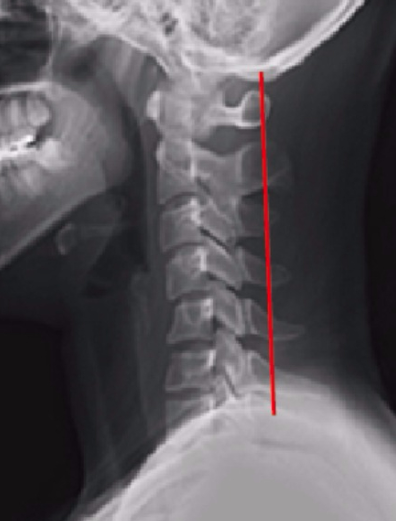

보통 건강한 목의 라인은

C커브를 유지하고 있는데요!

가장 안정된 상태의 라인이라고도 하더라구요!

하지만 자꾸 목을 숙이거나

고정된 자세로 자세나 바르지 않은 자세를 유지하게 된다면,

거북목과 일자목 현상이 나타납니다!

그렇게 척추뼈가 앞으로 머리의 하중으로

앞으로 쏠리게 되며 각도가 점점 커지게 되는데요!